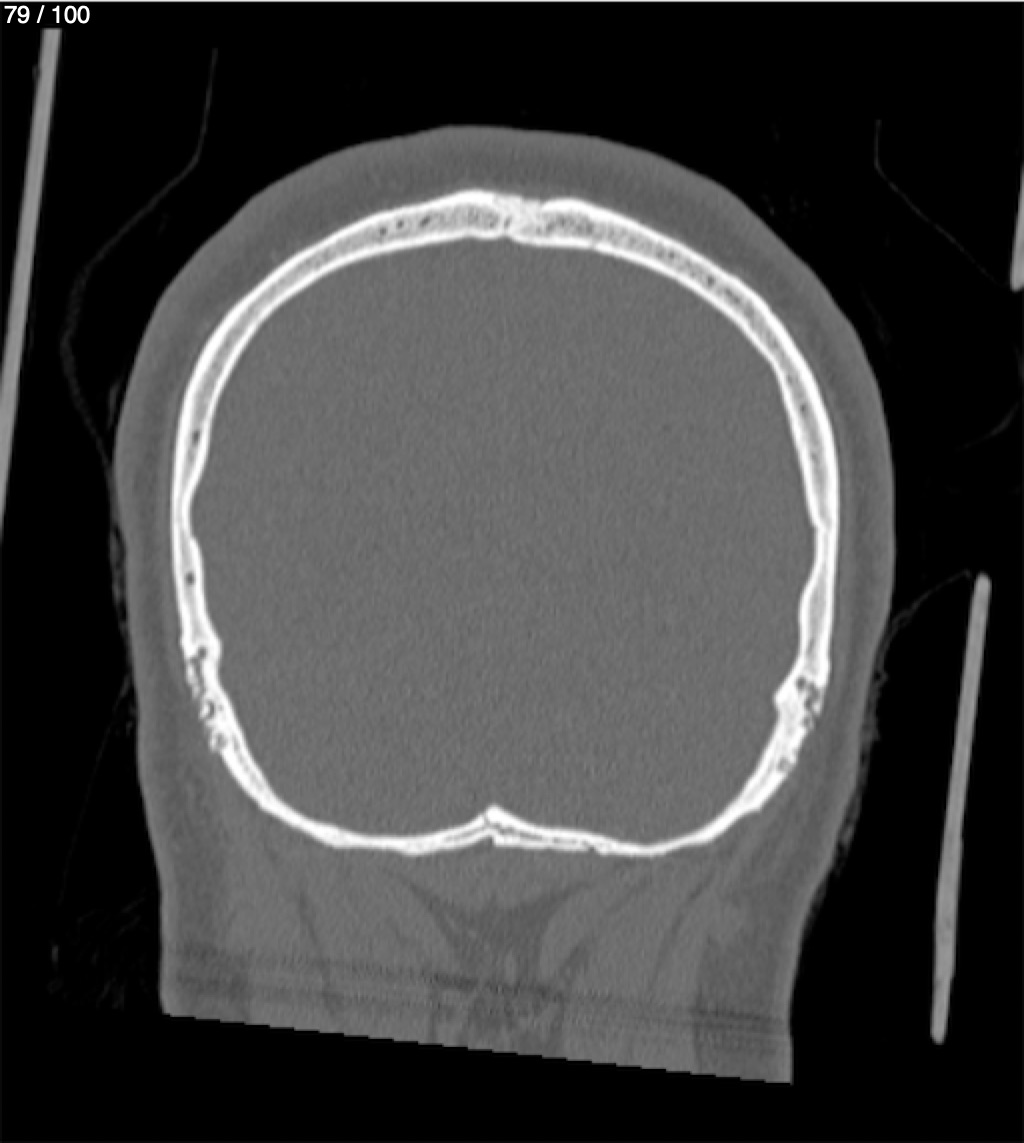

Reybet Garcia Fuentes 30A - T.C Craneo